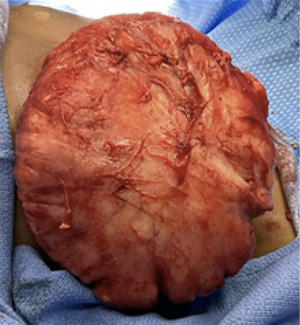

In the operating room, an inframammary incision was made, and flaps were elevated, similar in technique to starting a nipple sparing mastectomy (Figure 2). The dissection plane was difficult to discern because the pathology was diffusely infiltrated into the breast tissue. There was no discrete mass with clear borders. After excision, the only remaining breast tissue was <1 cm thickness directly under the nipple areolar complex (NAC) (Figures 2,3). This was spared in an effort to allow for future natural breast development and to maintain blood supply to the nipple. Final surgical pathology resulted as PASH, usual ductal hyperplasia, and focal apocrine metaplasia (Figure 4).